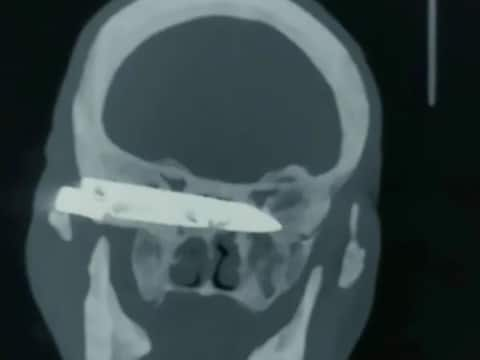

শানডং: ২৬ বছর পর বেরলো মাথায় গেঁথে থাকা ৪ ইঞ্চির ছুরি! দু-ধাপ অস্ত্রোপচারের পরে এখন দিব্যি হেঁটে বেড়াচ্ছেন বছর ৭৬-র বৃদ্ধ। একেবারে গায়েব মাথাব্যথাও! শল্যচিকিৎসার এই অভাবনীয় নমুনা দেখিয়েছেন চিনের শানডং প্রদেশের জিনানের শানডং কোয়ানফসান হাসপাতালের চিকিৎসকরা। দু ঘন্টার অস্ত্রোপচার করে মাথা থেকে বার করে আনা হয় ছুরি। চিকিৎসকরা জানিয়েছেন অপারেশান সম্পূর্ণ সফল হয়েছে। চিকিৎসায় সাড়া ও দিচ্ছেন বৃদ্ধ। দুওরিজে নামে ওই বৃদ্ধ পেশায় শ্রমিক ছিলেন। ৯০ এর দশকে একবার তিনি ভয়ানক এক হামলার শিকার হন। তখনই তাঁর মাথার ভিতর গেঁথে দেওয়া হয় ৪ ইঞ্চি লম্বা একটি ছুরি। অবাক কাণ্ড, শারীরিকভাবে সেই মুহূর্তে কোনও উপসর্গ দেখা যায়নি তাঁর। ২০১২ সাল পর্যন্ত মাথার মধ্যে ছুরি নিয়েই ঘুরে বেরিয়েছেন তিনি। ২০১২-র পর থেকে বিভিন্ন উপসর্গ দেখা দিতে শুরু করে তাঁর। মাথাব্যথা থেকে শুরু করে চোখের দৃষ্টিশক্তিও প্রায় হারিয়ে যেতে থাকে তাঁর। কিন্তু সেই সময়ও তার মাথায় অস্ত্রোপচার সম্ভব হয়নি। এর বেশ কিছু বছর পরে ওই ব্যক্তির বাড়ির এলাকায় স্বাস্থ্যপরীক্ষা করতে যান একটি চিকিৎসকদের দল। সেইসময় ধরা পড়ে ওই ব্যক্তির মাথায় গেঁথে রয়েছে একটি ছুরি! এলাকায় হাসপাতাল অপ্রতুল হওয়ায় তাঁকে নিয়ে যাওয়া হয় শানডং কোয়ানফসান হাসপাতালে। হাসপাতালের প্রধান চিকিৎসক ডঃ লিউ গুয়াংচুন জানান, অস্ত্রোপচারের সিদ্ধান্ত নেওয়া ছাড়া আর কোনও উপায় ছিল না। কারণ মাথা থেকে ছুরিটি না বের করতে পারলে ওই রোগীর যন্ত্রণার উপশম অসম্ভব ছিল। হাসপাতাল সূত্রে খবর, অস্ত্রোপচার করে তাঁর মাথা থেকে সম্পূর্ণভাবে বের করা গেছে ৪ ইঞ্চির একটি ছুরির ব্লেড। কয়েকদিন আগেই তাঁর ক্ষত সারানোর জন্য আরেকটি অস্ত্রোপচার করা হয়েছে। চিকিৎসায় ইতিবাচক সাড়া মিলেছে ওই বৃদ্ধের থেকে। আপাতত নিজেই হেঁটে চলে বেড়াচ্ছেন তিনি। ফিরে এসেছে চোখের দৃষ্টিশক্তিও। মুখ খুলে খাবার খেতে পারছেন তিনি। সোশ্যাল মিডিয়ায় ছড়িয়ে পড়েছে অস্ত্রোপচারের আগে ওই বৃদ্ধের মস্তিস্কের স্ক্যানের একটি ছবি। তাতে স্পষ্ট বোঝা যাচ্ছে মস্তিস্কে গেঁথে থাকা ছুরির অস্তিত্ব, যা দেখলে শিউরে উঠবেন যে কেউ!